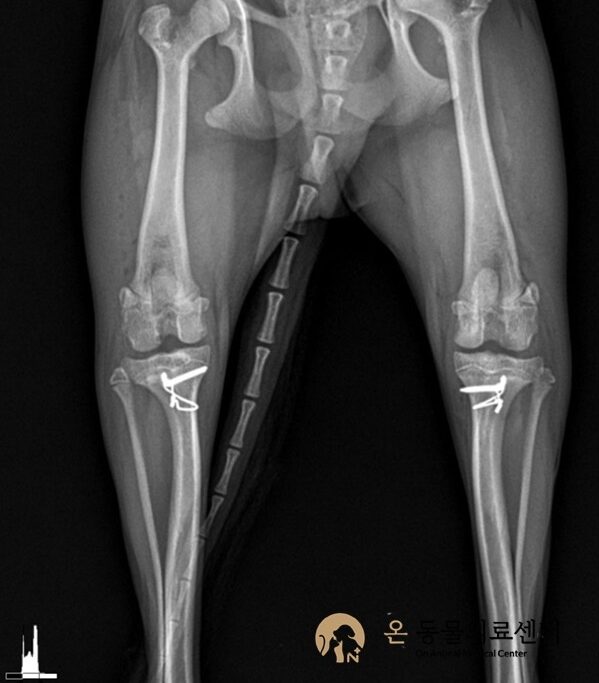

요척골골절

수술 전

수술 후